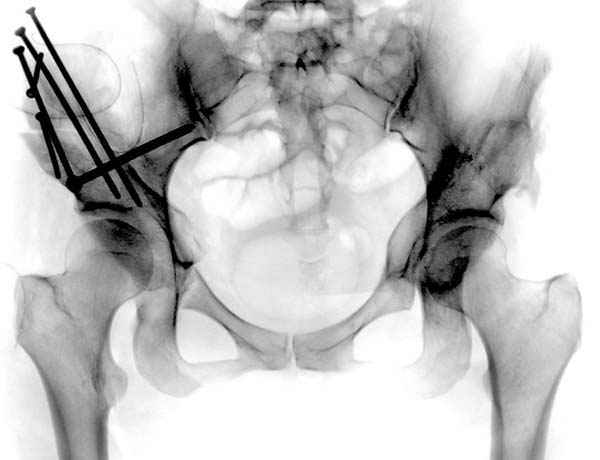

Но, занимаясь с этой патологией, собрал небольшой опыт в лечении остеоартрита, включая: периацетабулярную (ориентационно-корригирующую) остеотомию, и на проксимальной части бедра - valgus, varus, flexion and extension osteotomy и в комбинациях, базирующуюся на авангардных учениях Reinhold Ganz из Bern, на конгруентности сустава и увеличения контактной площади в суставе для уменьшения давления на площади хряща, При Вашем желании можно продемонстрировать результаты наших операций на слайдах.